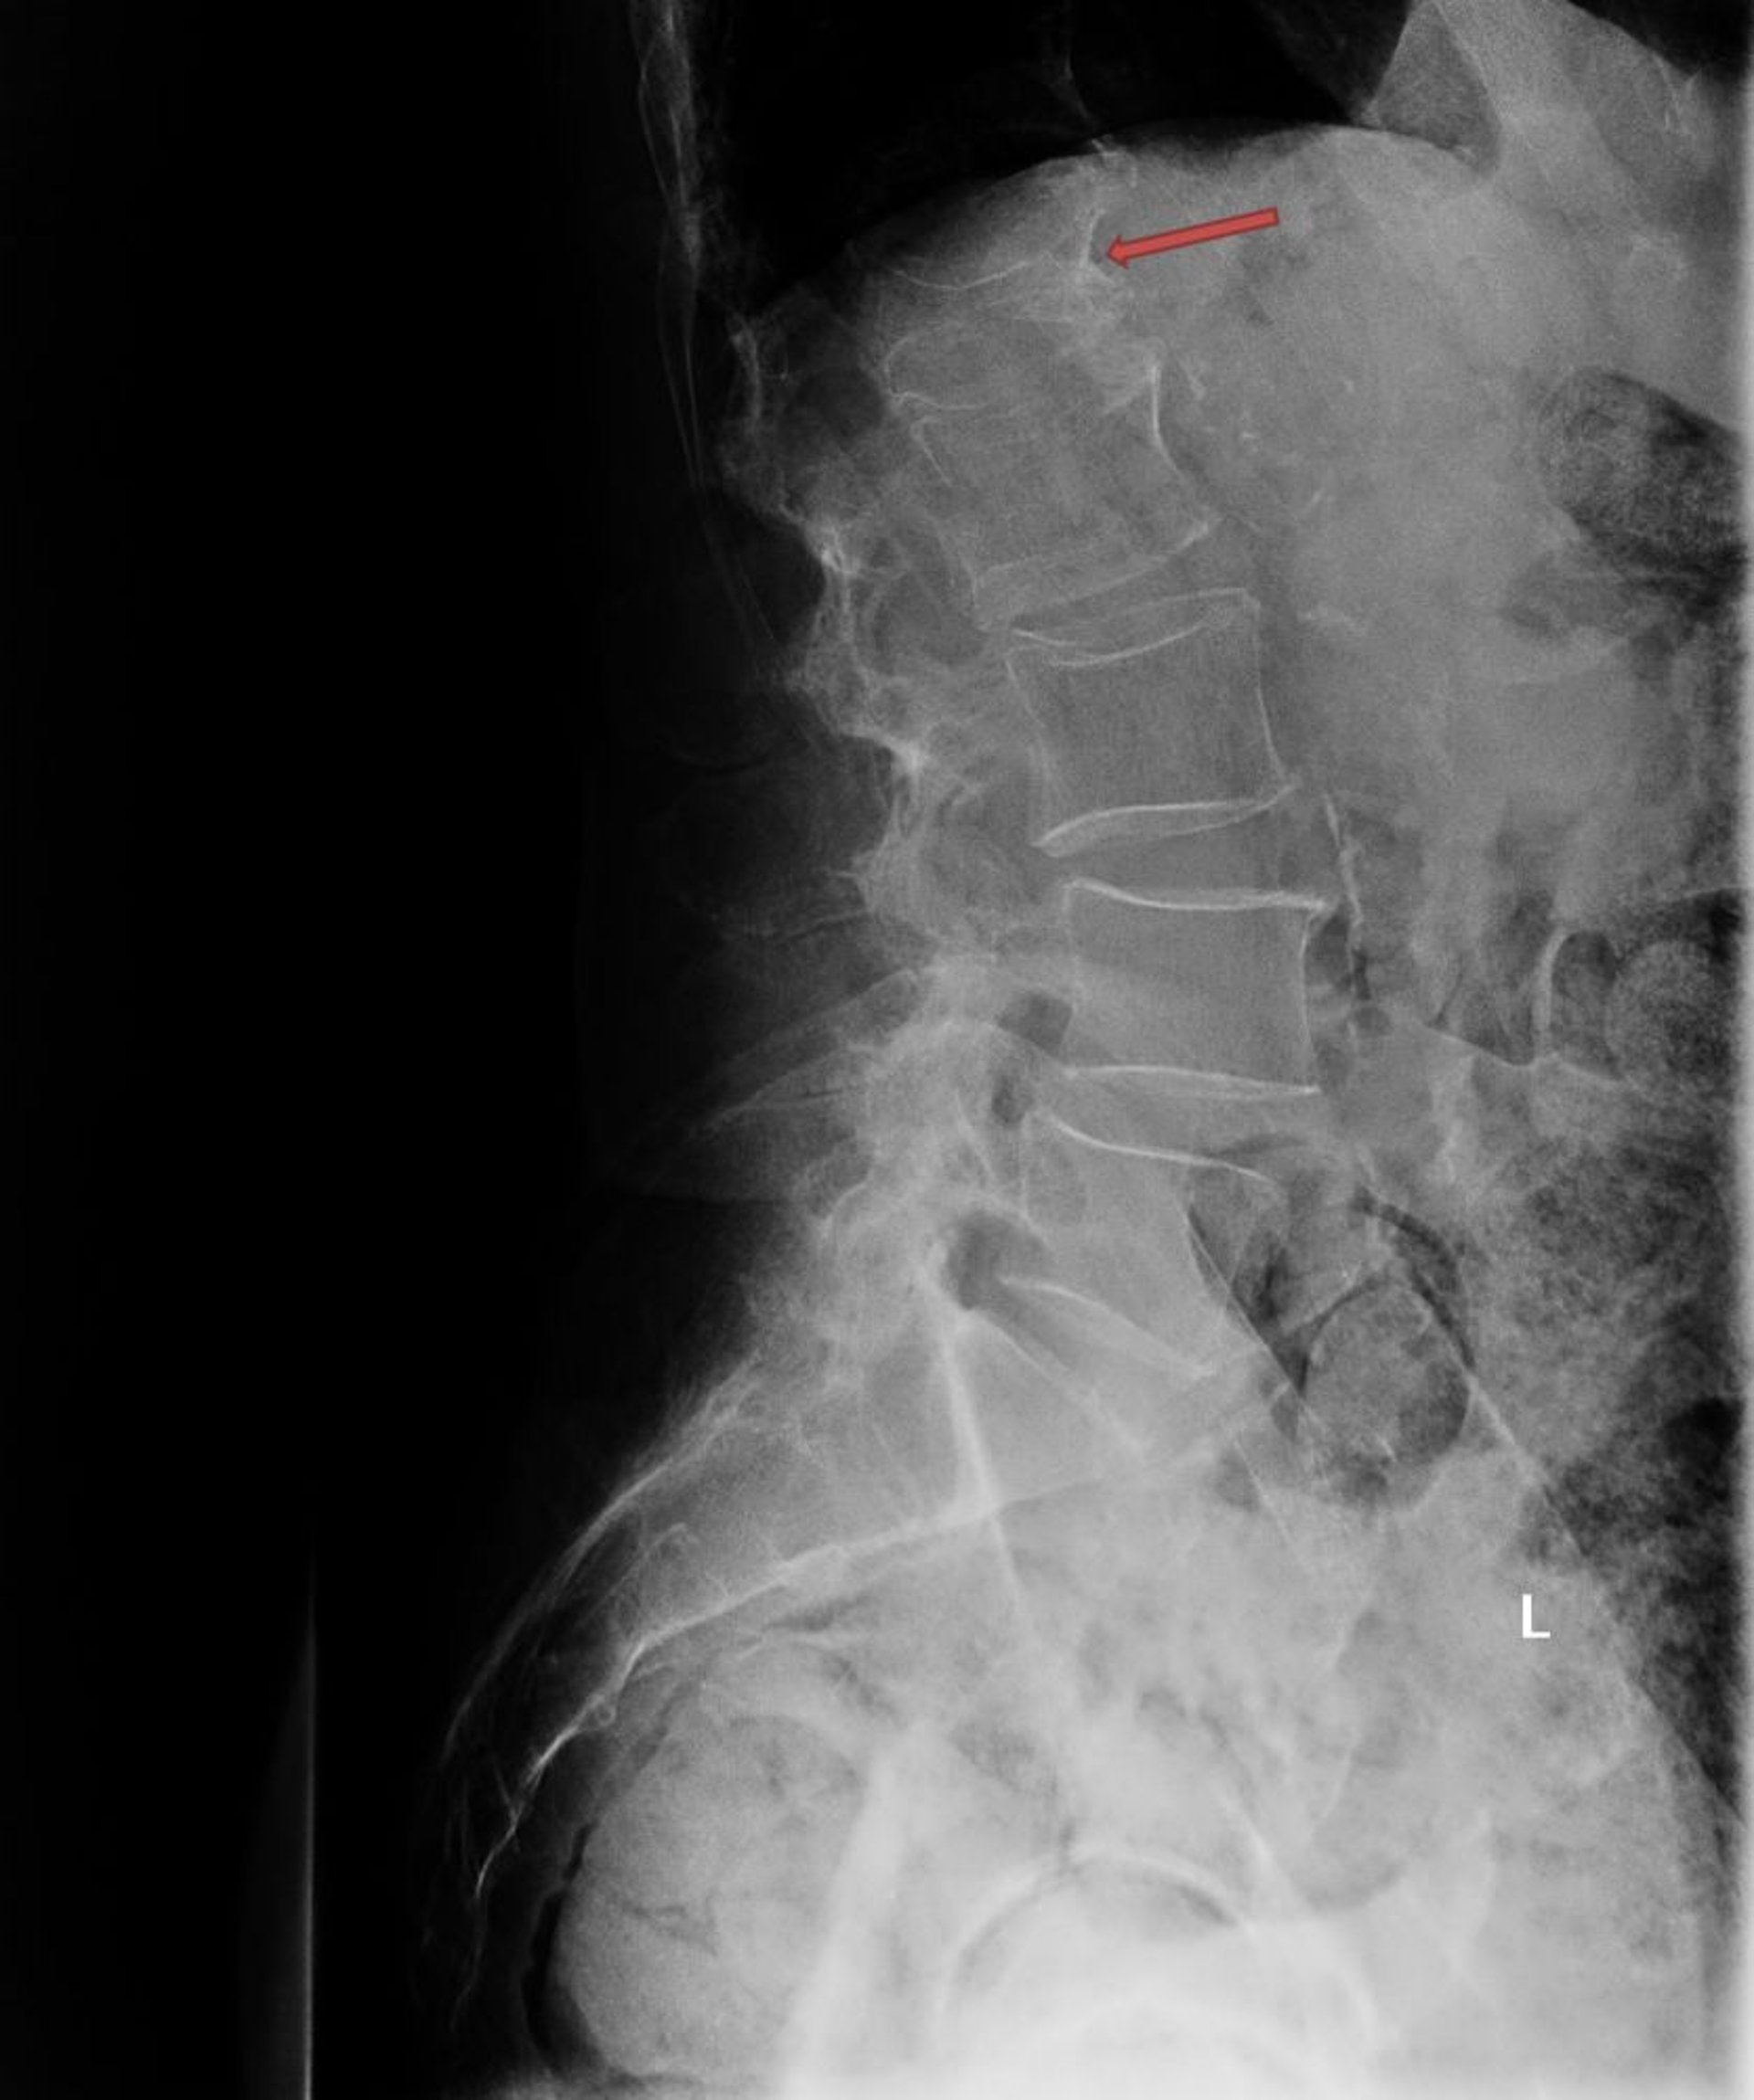

Остеопорозный компрессионный перелом

На данном рентгеновском снимке показан тяжелый остеопорозный компрессионный перелом первого поясничного позвонка (L1; стрелка).

Photo courtesy of Marcy B. Bolster, MD.